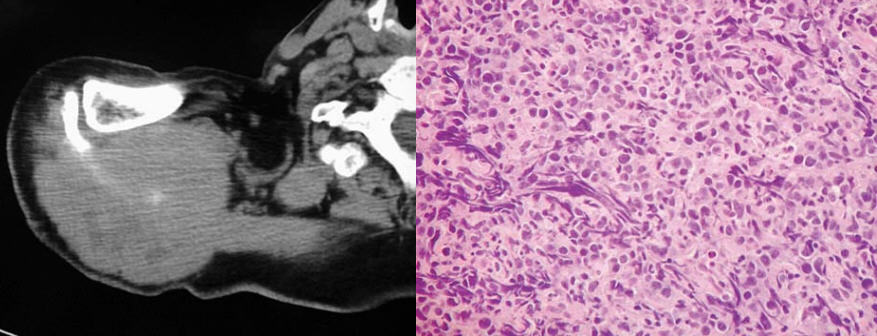

What percent of patients initially diagnosed with classic, high-grade osteosarcoma of the extremity have visible evidence of pulmonary metastasis on CT of the chest?

10-20%